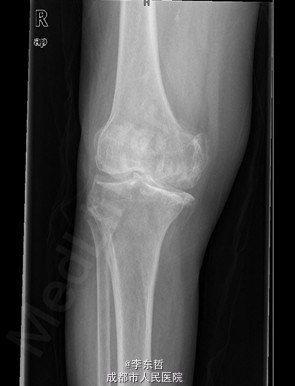

患者女,74岁,因“双膝疼痛20年,加重伴行走困难8年”入院。患者诉20年前开始出现双膝关节疼痛,负重行走、下楼时疼痛加重,休息后可缓解,尚可下蹲。自行购买止痛药口服,关节腔内注射玻璃酸钠、理疗等处理,疼痛时有缓解。但症状反复发作。8年前疼痛加重且行走困难,扶拐行走仅能坚持约10余米,上下楼梯艰难,下蹲不能,以左侧为重。遂来院就诊。

查体:跛行步态,双膝关节屈曲内翻畸形,双膝内侧间隙压痛,双膝髌股关节间隙压痛,左膝伸-20°,屈110°内翻10°。右膝伸-20°,屈110°内翻10°,双膝屈伸活动时髌骨下摩擦感(+)。 辅助检查:X片示双侧髌股关节内侧间室变窄,关节边缘骨赘增生,软骨下骨硬化。

入院诊断:1、左膝骨关节炎伴屈曲内翻畸形; 2、右膝骨关节炎伴屈曲内翻畸形; 诊疗计划:1、向患者及家属交待病情及注意事项。2、向上级医生汇报患者病情。3、完善相关术前检查;4、择期手术。